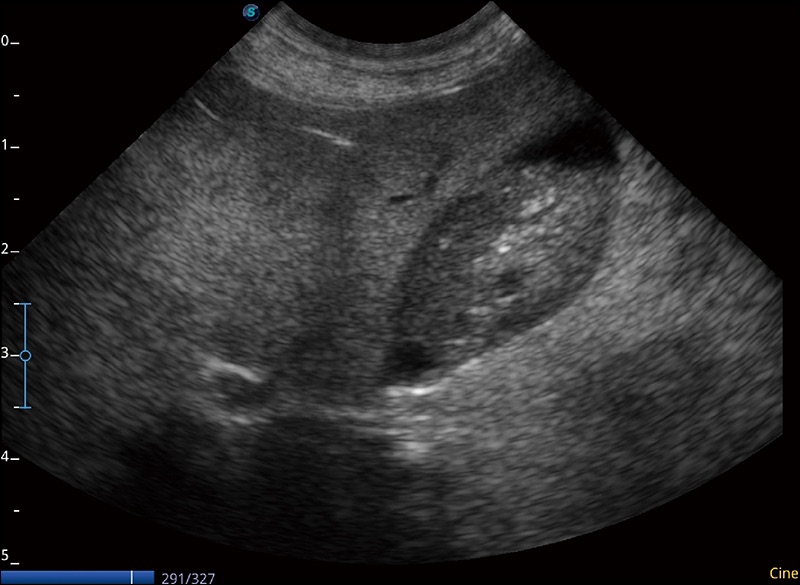

临床图